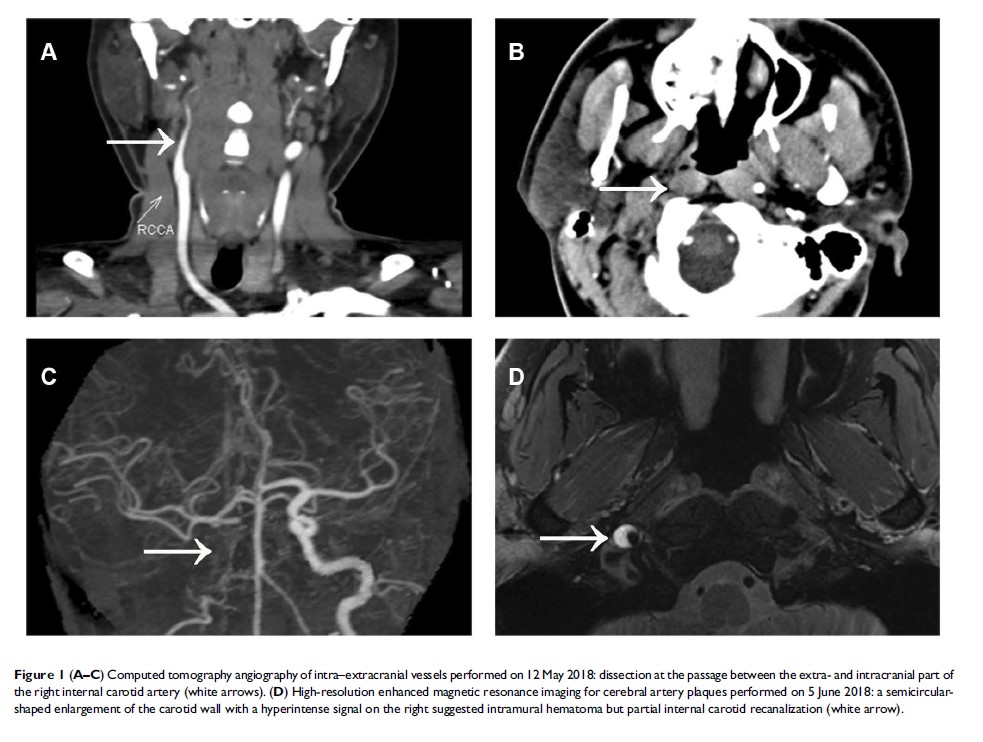

三叉神经自主性头痛作为 IV 型埃勒斯-当洛斯综合征的唯一初始症状